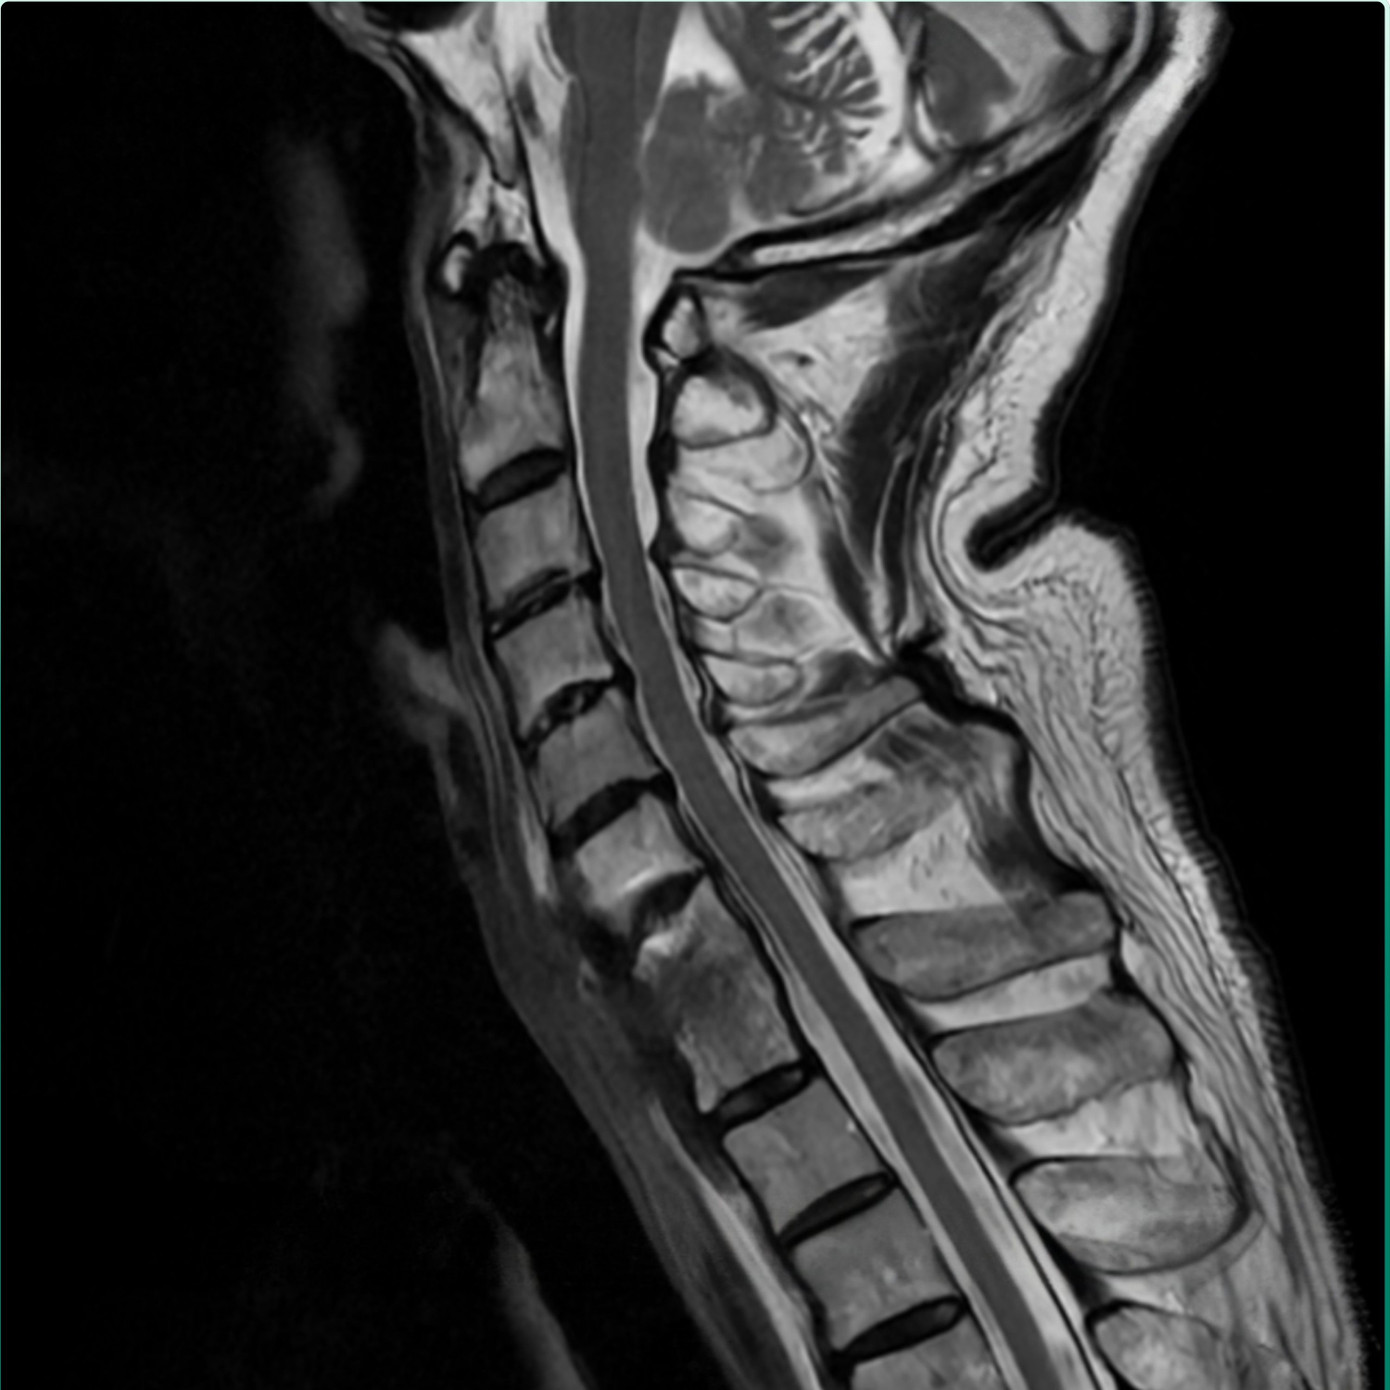

Theo PGS.TS.BS Hà Kim Trung (Chuyên gia phẫu thuật cột sống - Phó Giám đốc Y khoa BVĐK Hồng Ngọc - Phúc Trường Minh) phân tích: Qua kết quả chụp MRI cho thấy bệnh nhân bị nhiễm trùng cột sống cổ. Theo nhiều nghiên cứu y văn trên thế giới đây là tình trạng hiếm gặp, chỉ chiếm khoảng 2 - 7% trong tổng số các ca nhiễm trùng cơ xương khớp. Có thể xuất phát từ chấn thương, biến chứng sau phẫu thuật hoặc lây lan qua đường máu. Tình trạng viêm, áp xe phá hủy thân đốt sống và đĩa đệm C7/T1, tạo dải xơ co kéo khiến cổ bệnh nhân luôn trong tư thế gập, không thể xoay, ngửa. Nếu không phẫu thuật sớm, nguy cơ liệt vận động là rất cao.

Tình trạng xơ dính và đốt sống bị biến dạng trước phẫu thuật